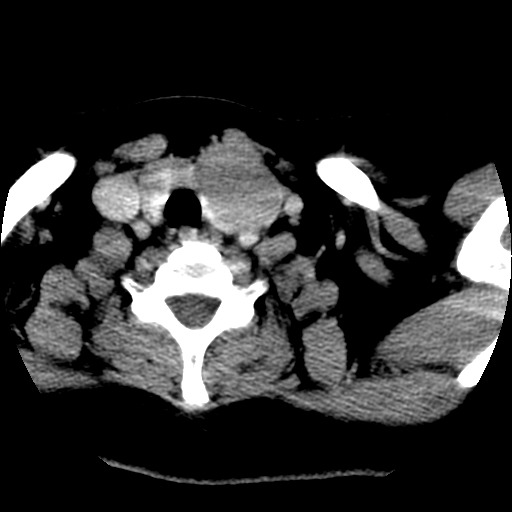

左右叶都有,峡部也受累,有钙化,考虑结甲可能性大。

考虑右叶结节性甲状腺肿,伴左叶钙化。主要(1)密度均匀,边境清。(2)病灶与血管界限清。

边界清,无明显强化,考虑考虑甲状腺腺瘤